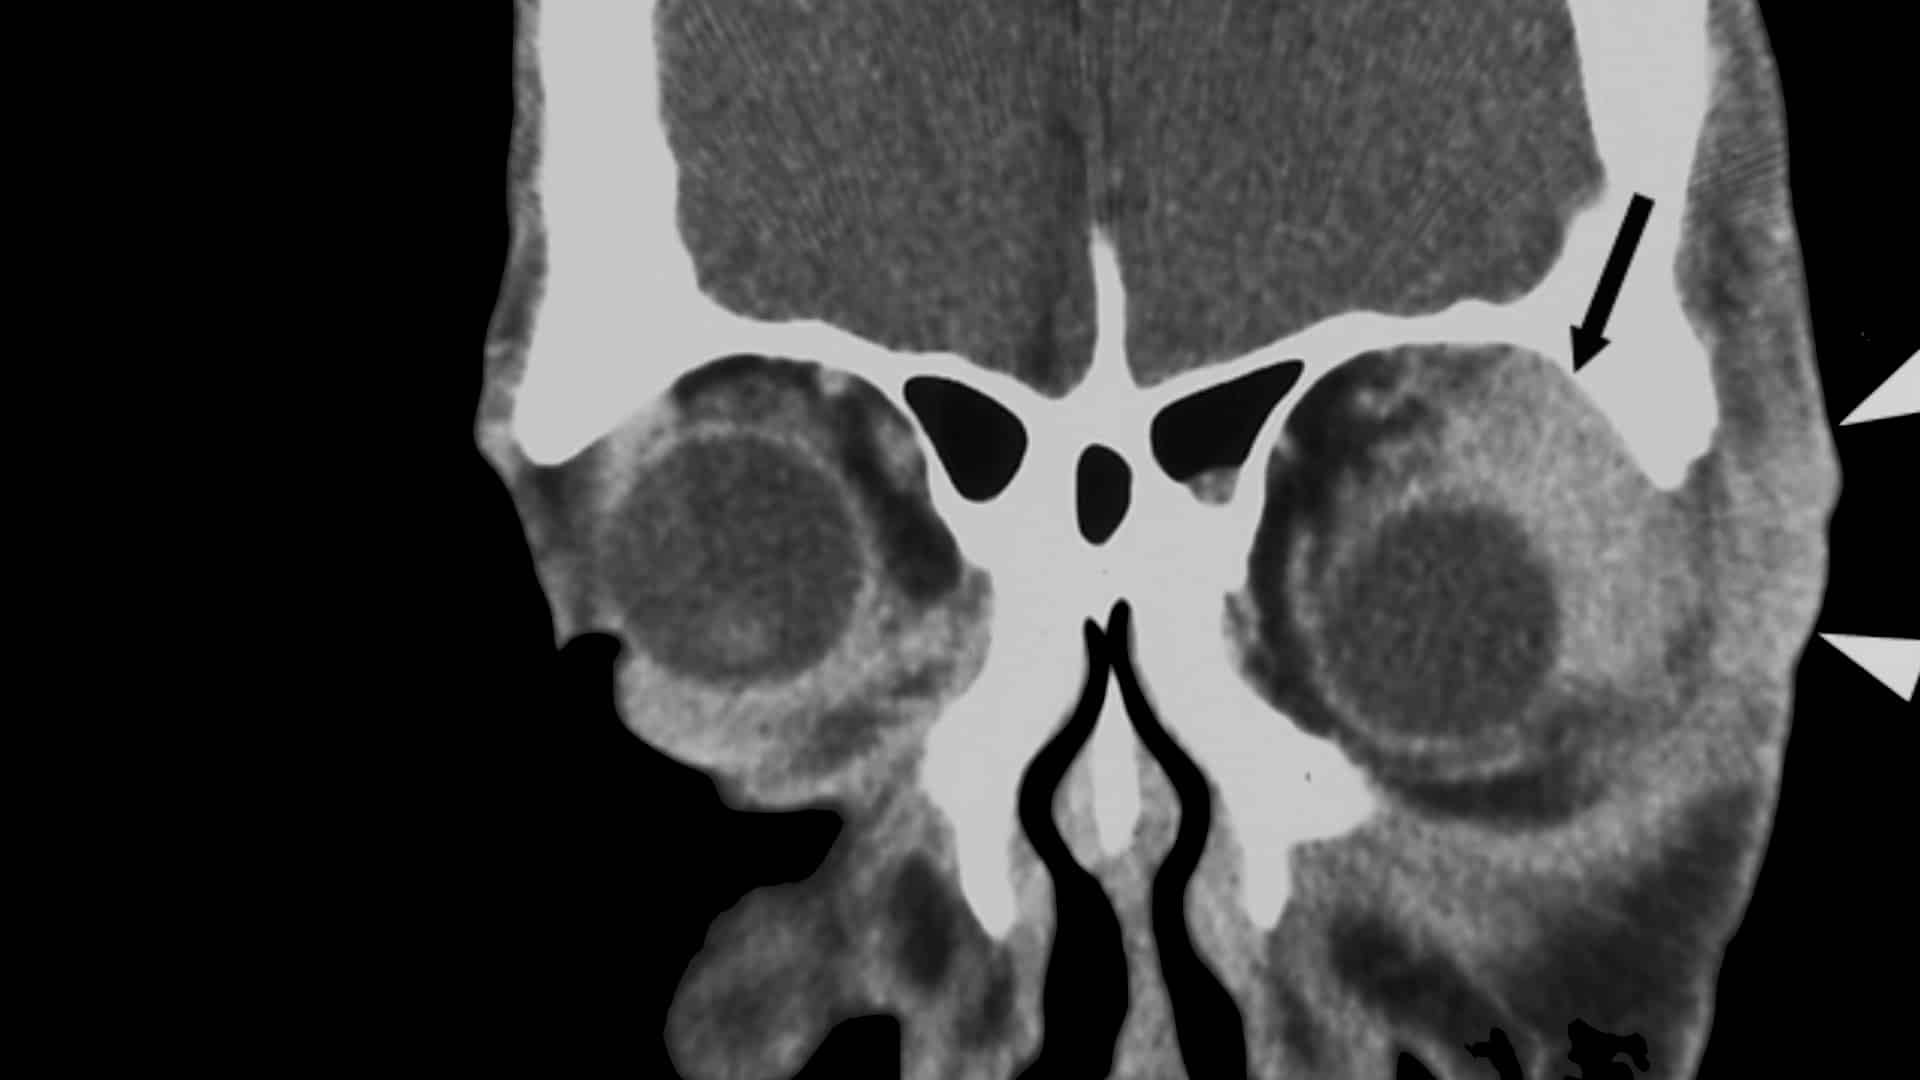

Benefits of Turmeric Curcumin for Inflammatory Orbital Pseudotumor

From conjunctivitis to uveitis to a low-grade form of non-Hodgkin’s lymphoma, there is something in...

From conjunctivitis to uveitis to a low-grade form of non-Hodgkin’s lymphoma, there is something in the spice turmeric with dramatic anti-inflammatory effects.